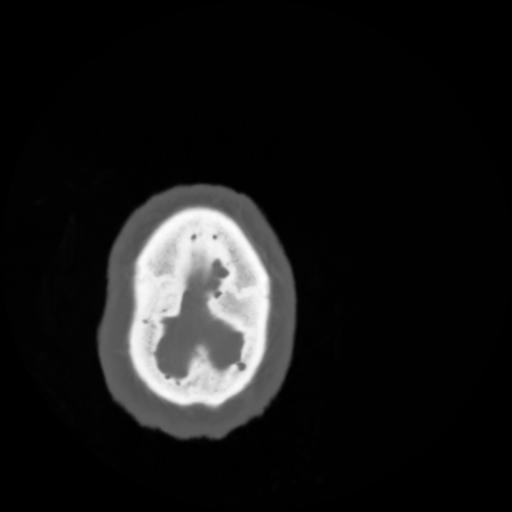

4 CEREBRO,,Vol,0.5,CEREBRO,,